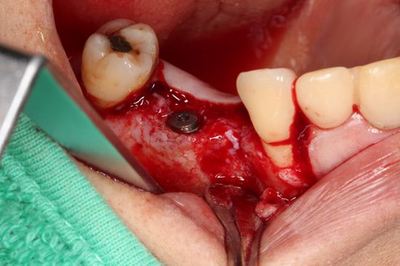

左上臼歯部のCT画像です。

2本の埋入計画を立てますが第一小臼歯部分に骨欠損があります。